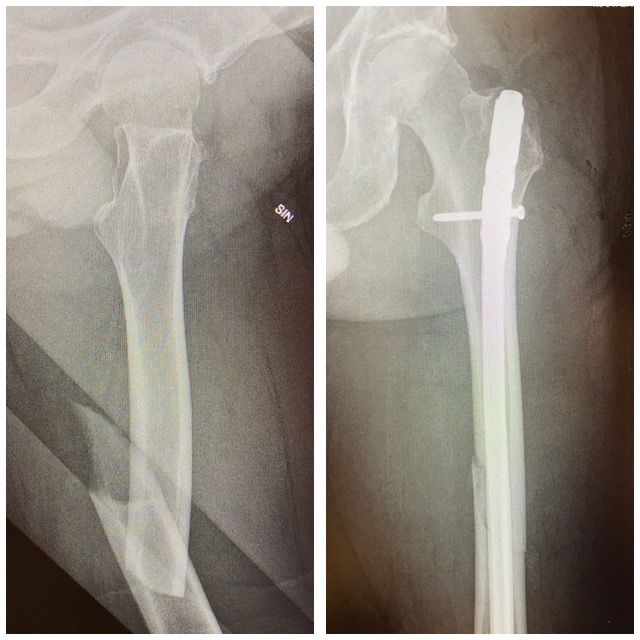

Lonkkamurtuma

Reisimurtuma

Ennen – jälkeen